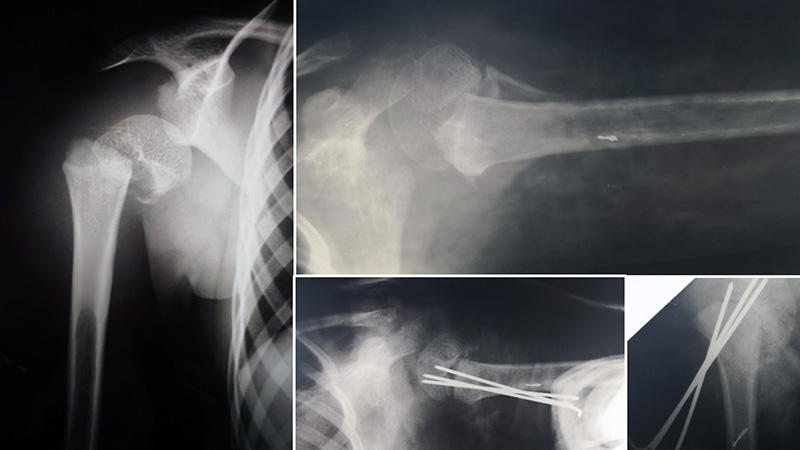

Un trauma all’età di sei anni ha compromesso la cartilagine di accrescimento dell’omero in un giovane paziente, causando una progressiva discrepanza di 8,5 cm nella lunghezza dell’arto al raggiungimento dell’età adulta. L’evento traumatico, inizialmente trattato come una frattura, ha avuto conseguenze a lungo termine sul normale sviluppo osseo.

Con il team Kirienko, abbiamo eseguito con successo un’osteotomia dell’omero con applicazione di fissatore esterno tipo Ilizarov. Questo approccio ha permesso di ottenere un allungamento progressivo e controllato dell’osso.